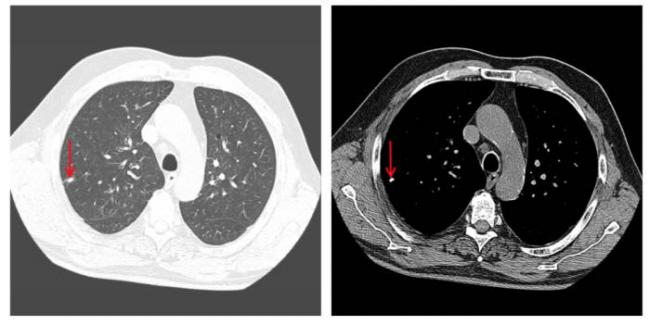

Как очаги в легких выглядят на снимке КТ?

Чтобы человек несведущий смог разобраться в результатах КТ, следует знать о нюансах чтения снимков. Рассмотрим самые актуальные:

- Очаговые образования представляют собой участки белого цвета на черном фоне (на снимке-негативе). В реальности пораженная область, скорее всего, имеет более темный цвет, чем здоровые ткани легкого.

- Если врач заметит на снимке участки кальцинирования или обызвествления (капсул, пропитанных солями кальция) вокруг очага, это может быть признаком доброкачественности образования. Кальцинаты по цвету похожи на кости скелета, видимые на этом снимке. Такие явления часто обнаруживаются после затяжных простудных заболеваний, бронхитов или уже излечененного туберкулеза и представляют собой некий шрам на легких. Пациента с образованием, на котором заметны признаки кальцината, пульмонологи обычно просят раз в полгода делать контрольные снимки.

- В случае, когда образование представляет собой так называемое «облачко» или очаг по типу «матового стекла», требуется более предметное обследование. Внешне оно выглядит как затуманенная область с размытыми границами. В ряде стран пациентам с такими образованиями сразу рекомендуется операция, даже если оно не растет. Уже доказано, что в 80% случаев такие очаги являются предраковым состоянием легких. Альтернатива немедленной операции — постоянное наблюдение с контрольными снимками раз в полгода-год.

Очаговые изменения

Очаговые изменения в лёгких могут быть разного размера. Очаги мелкого диаметра 1-10 мм выявляются при различных диффузных патологиях лёгочной ткани. Очаги с высокой плотностью и довольно чётки краями в основном наблюдаются в интерстиции лёгкого. Различные очаги низкой плотности, напоминающие матовое стекло, с нечёткими контурами возникают при патологических изменениях в респираторных отделах дыхательных органов.

Нужно учитывать, что плотность и размер очагов имеет слабое диагностическое значение. Для постановки диагноза более важным может быть распределение патологических процессов в лёгочной ткани: